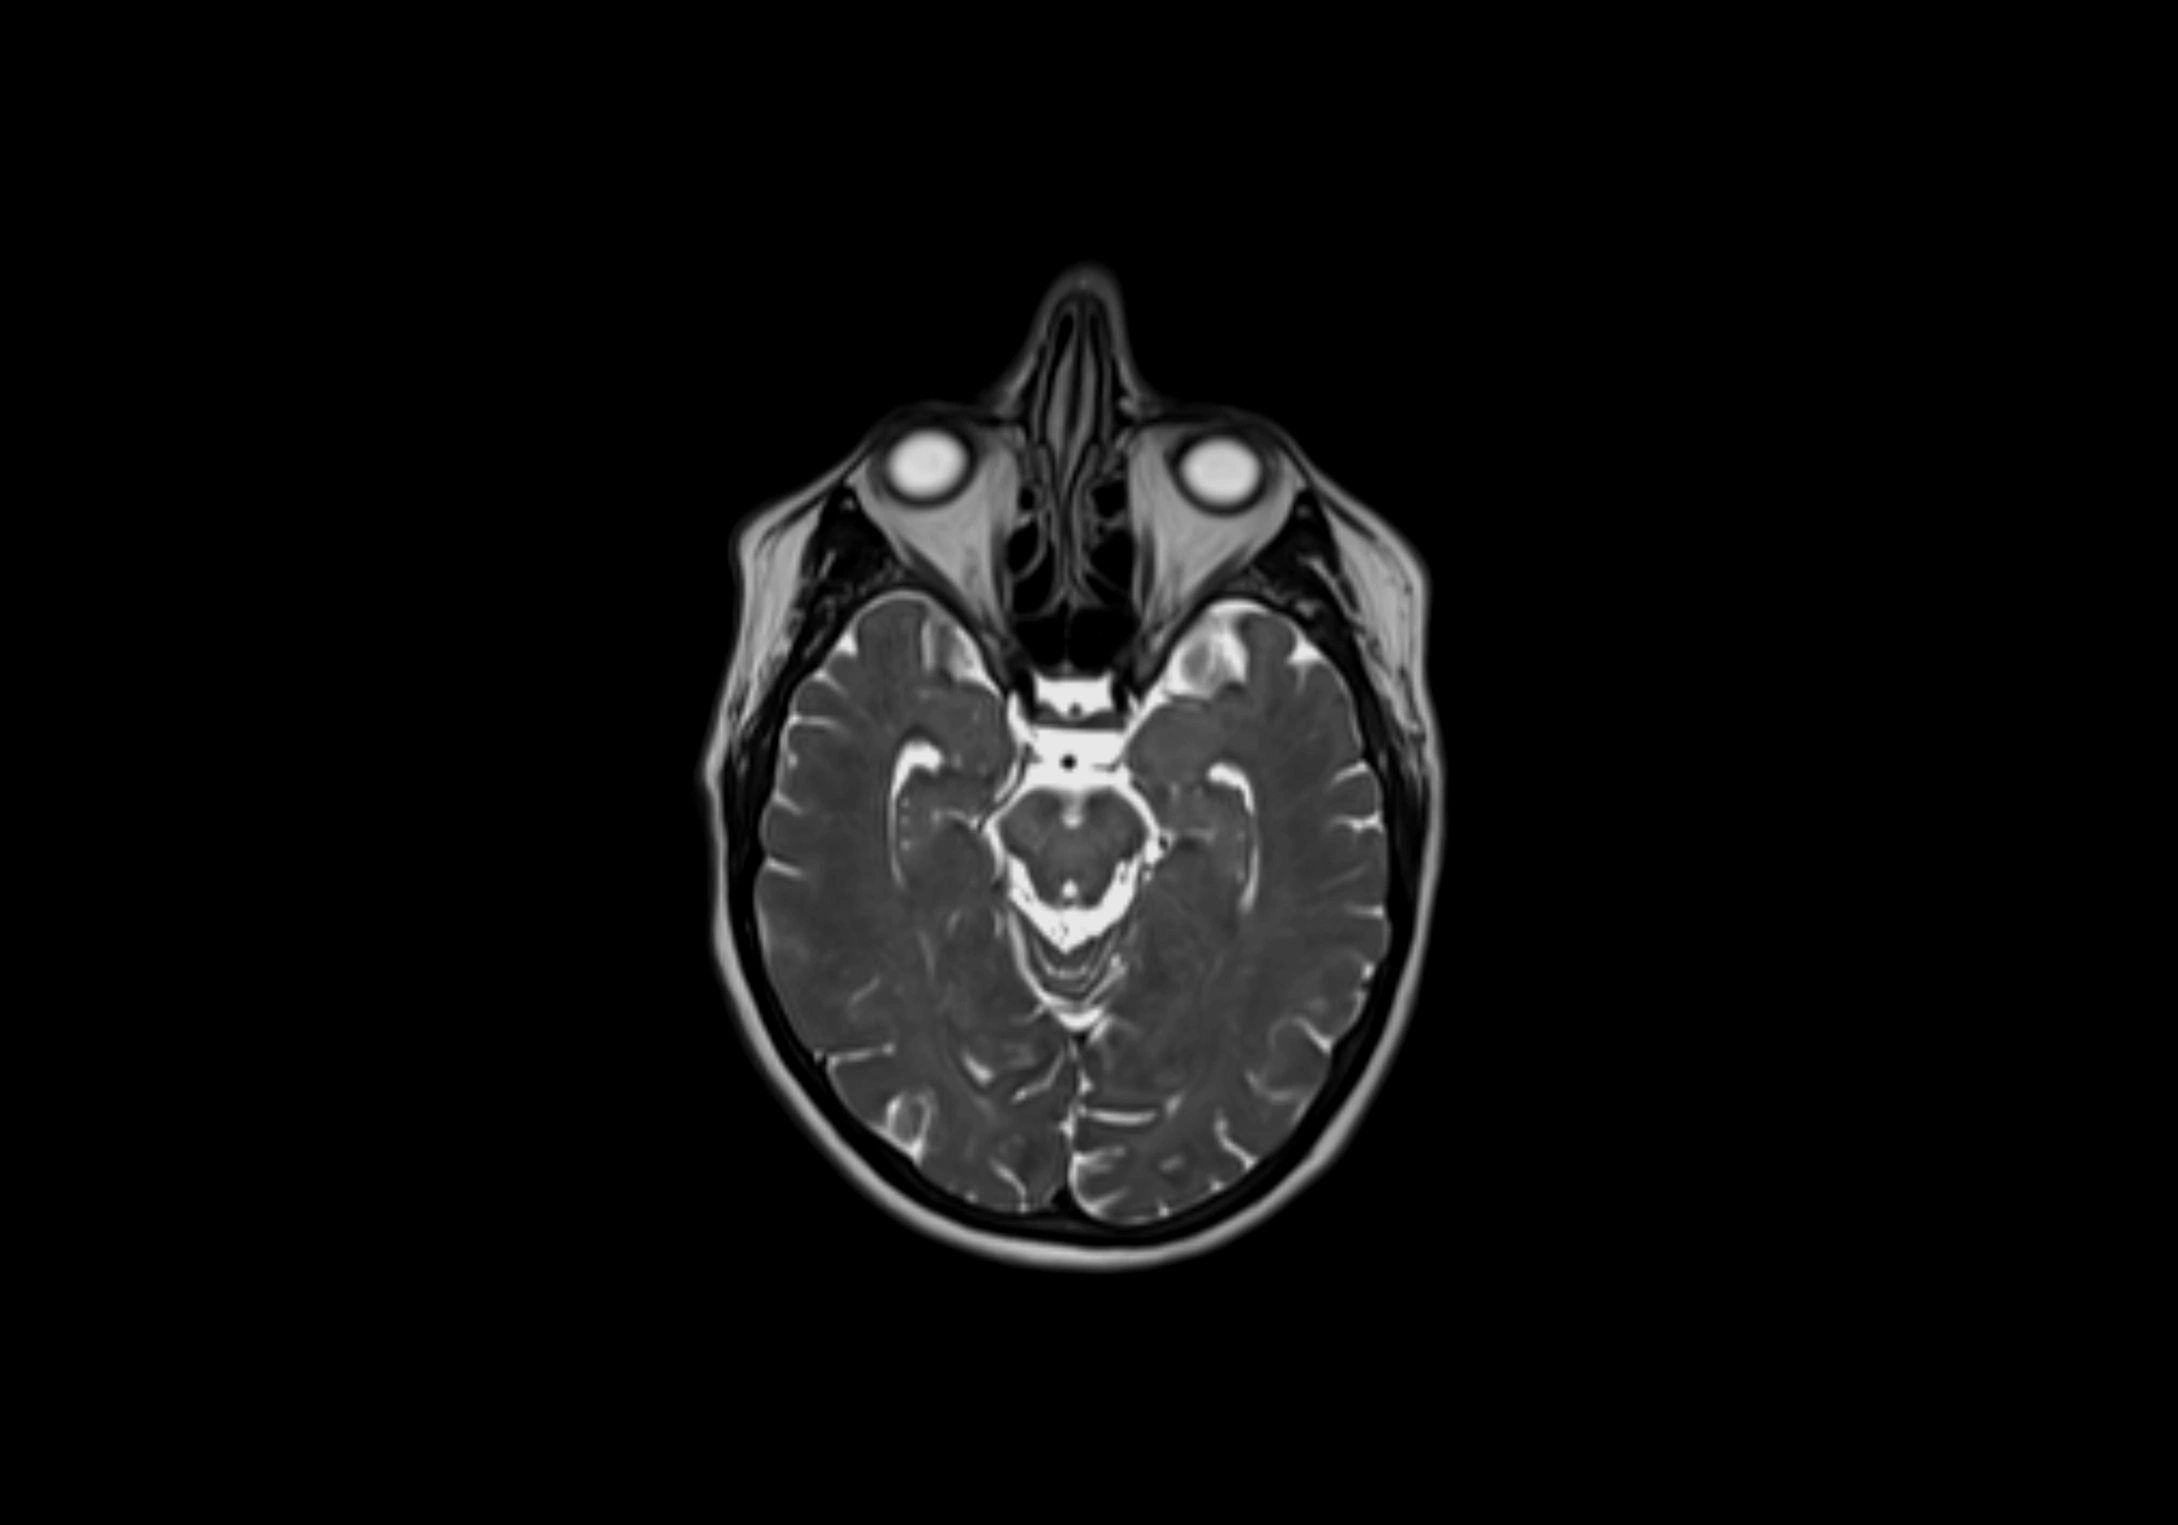

MRI Appearance

T2-weighted images:

• Nodes show intermediate signal, with surrounding fat bright

• Useful for detecting edema, inflammation, or infiltration

• Fatty hilum may appear slightly hyperintense relative to cortex

MRI images

image